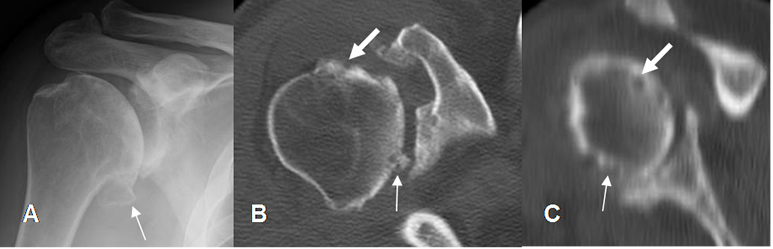

Fig 97. Pinzamiento postero superior.

A: TAC axial: Lesión osteocondral en la parte posterior de la cabeza humeral.

B: TAC reconstrucción coronal y C: RM sagital en T1. Lesión osteocondral en el borde posterosuperior de la cabeza humeral, por pinzamiento.